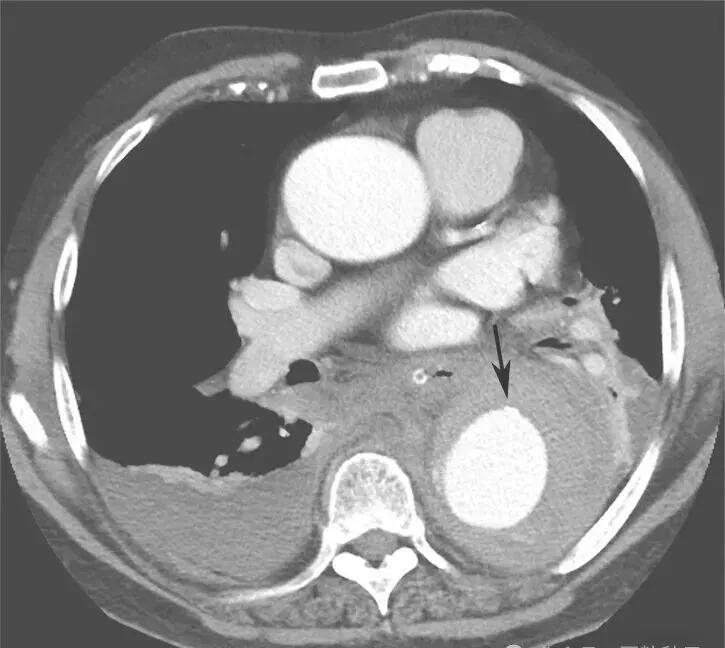

入院后紧急行血管螺旋CT扫描+三维重建,以明确主动脉病变。血管螺旋CT扫描+三维重建如图2所示。降主动脉至腹主动脉夹层动脉瘤并壁间血肿形成(累及主动脉弓至肾动脉开口平面)。升主动脉管径约4.9cm。主动脉弓与降主动脉弥漫管腔增粗,周围可见弥漫壁间血肿形成,向下延伸至肾动脉平面。主动脉弓上三大分支开口与显影良好。主动脉弓外径为5.4cm,内径约3.8cm。降主动脉外径为7.5cm,内径为4.8cm。气管隆嵴下平面降主动脉左前壁局限性钙化上方有一个溃疡,溃疡内有少量对比剂充盈。胸主动脉下段向右侧明显迂曲。腹主动脉与肾动脉平面上方可见内膜片与真假腔形成,假腔内有少量造影剂充填。腹腔干动脉和肠系膜上动脉开口未见受累。右肾动脉开口部分受累,左肾动脉开口未见受累。腹主动脉下段、双侧髂内外动脉血管形态良好。双侧胸腔中等量积(血)液(图3箭头处)。

图2 主动脉CT螺旋扫描+三维重建

图3 双侧胸腔积(血)液